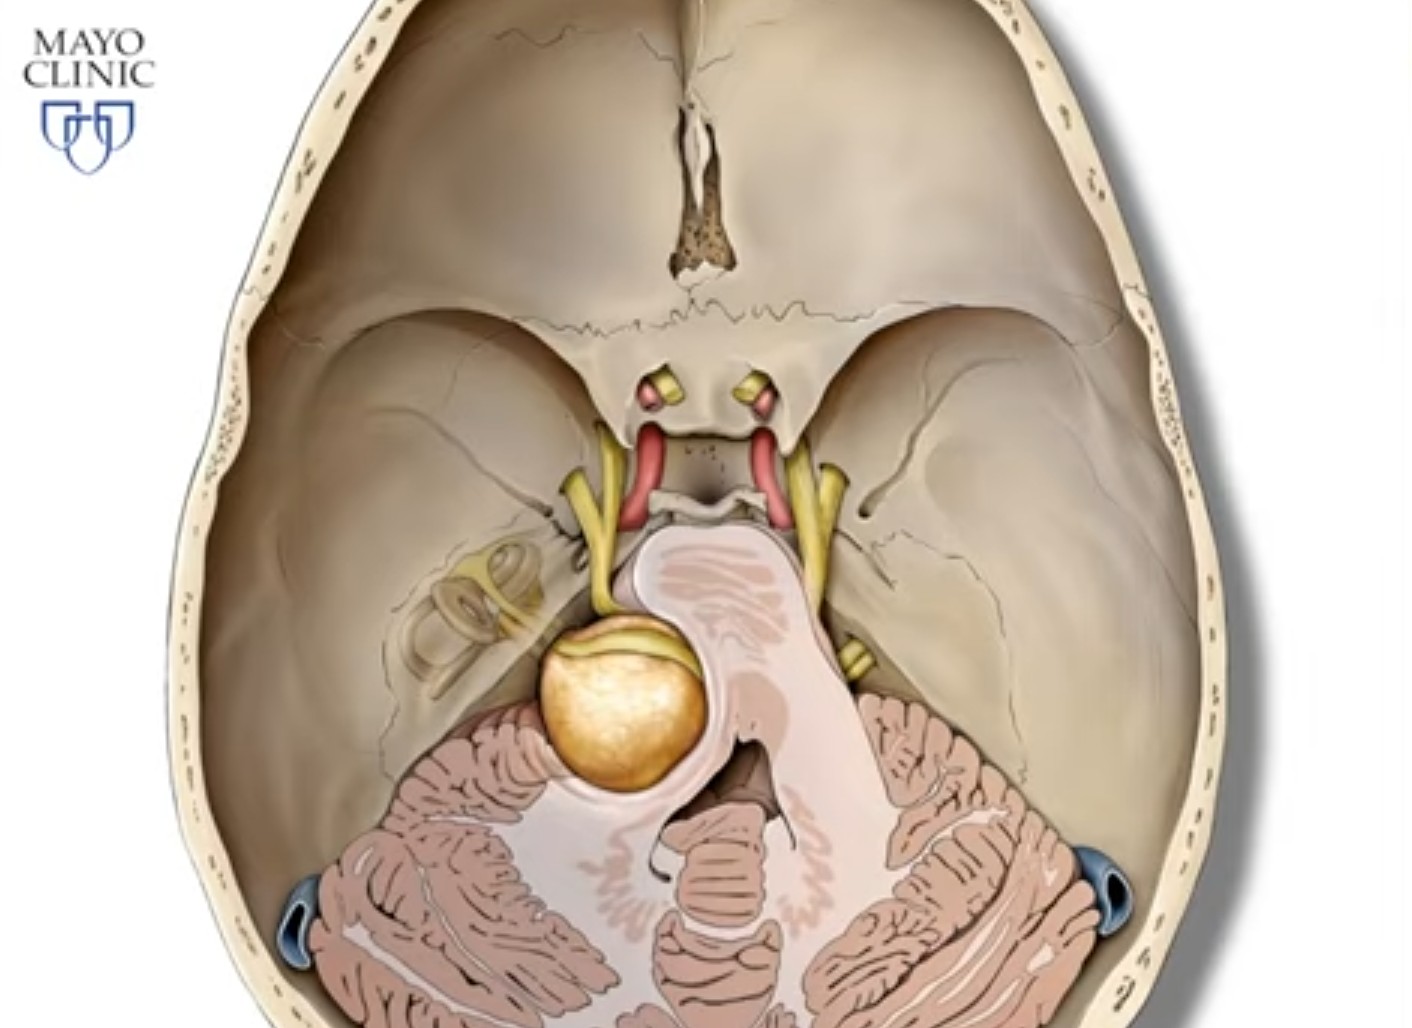

Вблизи преддверно-улиткового нерва проходят: ствол лицевого нерва (VII), тройничный нерв (V), отводящий (IV), языкоглоточный (IX) и блуждающий (X) нервы . По мере роста невриномы в клинической картине могут возникать симптомы сдавления этих нервов, а также прилежащих структур ствола мозга.